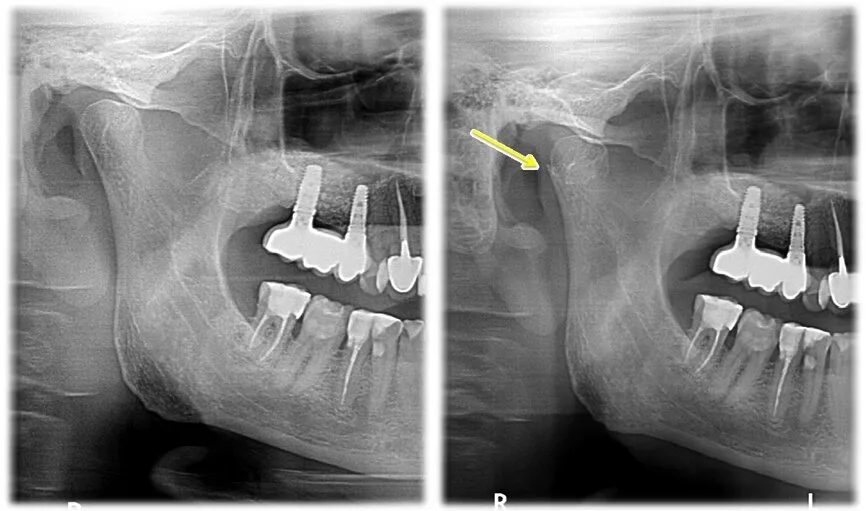

Standardowe zdjęcie panoramiczne OPG i zdjęcie cefalometryczne to płaskie projekcje – sumują wszystkie struktury na jednej płaszczyźnie i nie pozwalają precyzyjnie ocenić kształtu wyrostka kłykciowego, stopnia erozji ani symetrii przestrzeni stawowych po obu stronach. Lekarz widząc na OPG opis 'spłaszczony kłykieć' nie jest w stanie bez CBCT ocenić, czy to artefakt projekcji, normalny wariant anatomiczny, czy rzeczywista resorpcja wymagająca interwencji.

Rekonstrukcja CBCT stawów dostarcza lekarzowi przekrojów w trzech płaszczyznach dla każdego stawu osobno. W płaszczyźnie strzałkowej widoczna jest geometria wyrostka kłykciowego: jego wysokość, szerokość i kąt pochylenia do osi pionowej. Spłaszczenie powierzchni kłykcia (remodeling) lub wyraźne ubytki kostne (resorpcja) są od razu czytelne jako zmiany kształtu w porównaniu do fizjologicznego owalu.

W przekrojach czołowych lekarz ocenia symetrię przestrzeni stawowych – odległość między głową żuchwy a panewką stawową. Niesymetryczna przestrzeń stawowa koreluje z asymetrią okluzji i jest jedną z przyczyn jednostronnego bólu stawu. CBCT pozwala zmierzyć tę asymetrię liczbowo, a nie tylko wizualnie.